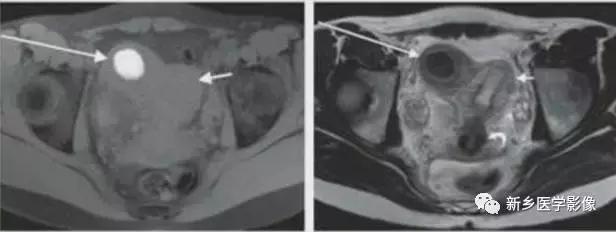

IV:双角子宫

左图:完全双角子宫,分隔延伸至宫颈内口或外口。

右图:部分双角子宫,分隔局限于宫底。

子宫上部不融合,下部及宫颈融合。宫底凹陷>1cm,双侧宫角分离。宫颈有或无分隔,25%伴有纵隔。

双角子宫:不完全型,宫底凹陷,上部子宫不融合,子宫纵隔未达宫颈内口水平。

双角子宫:完全型